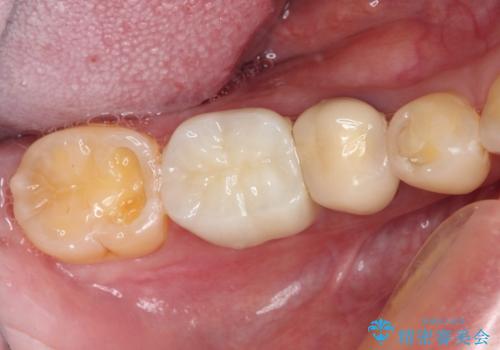

奥歯が欠けてしまった オールセラミッククラウンによる補綴治療

- 奥歯が欠けてしまった事を主訴として来院した患者様です。

頬側の欠けている範囲が大きく、以前治療した詰め物も大きいため、詰め物を外してむし歯を除去し、

形を整えて一度仮歯に置き換え、フルジルコニアクラウンにて補綴しました。

高強度のフルジルコニアクラウンは、強いかみ合わせでも壊れにくいです。

また審美的にも満足していただけました。